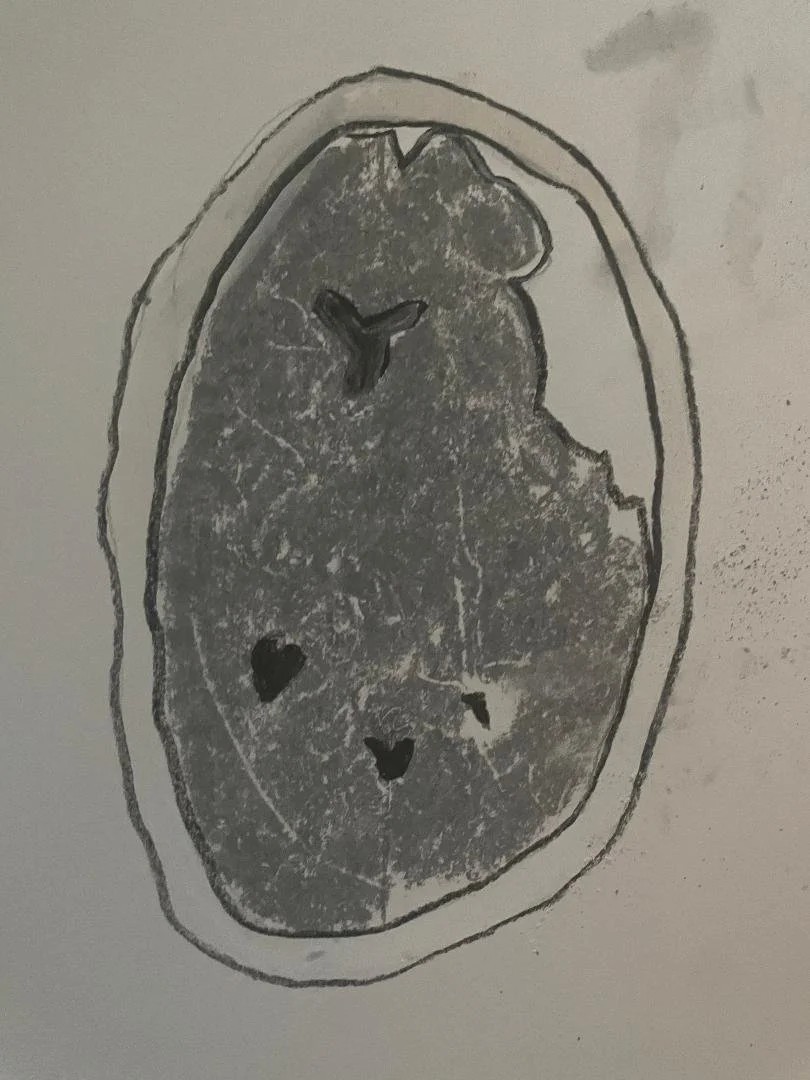

Arachnoid cyst